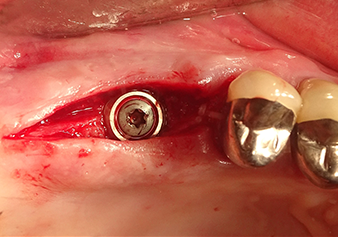

Implantation and prosthetic restoration

To move the augmentation material in the direction of the maxillary sinus atraumatically, the implant was inserted very slowly by hand (Fig. 9). In the process, the membrane was pushed in the cranial direction once again. After two months, the surgical site healed without irritation. Six months later, the x-ray check showed a significant increase in opacity as an indication of ossification (Fig. 10). The prosthetic restoration was carried out with a metal-ceramic crown.

Situation after insertion of the implant

Fig.9: Situation after insertion of the implant (length: 10 mm, prosthetic platform: 6.5 mm) immediately before suturing.